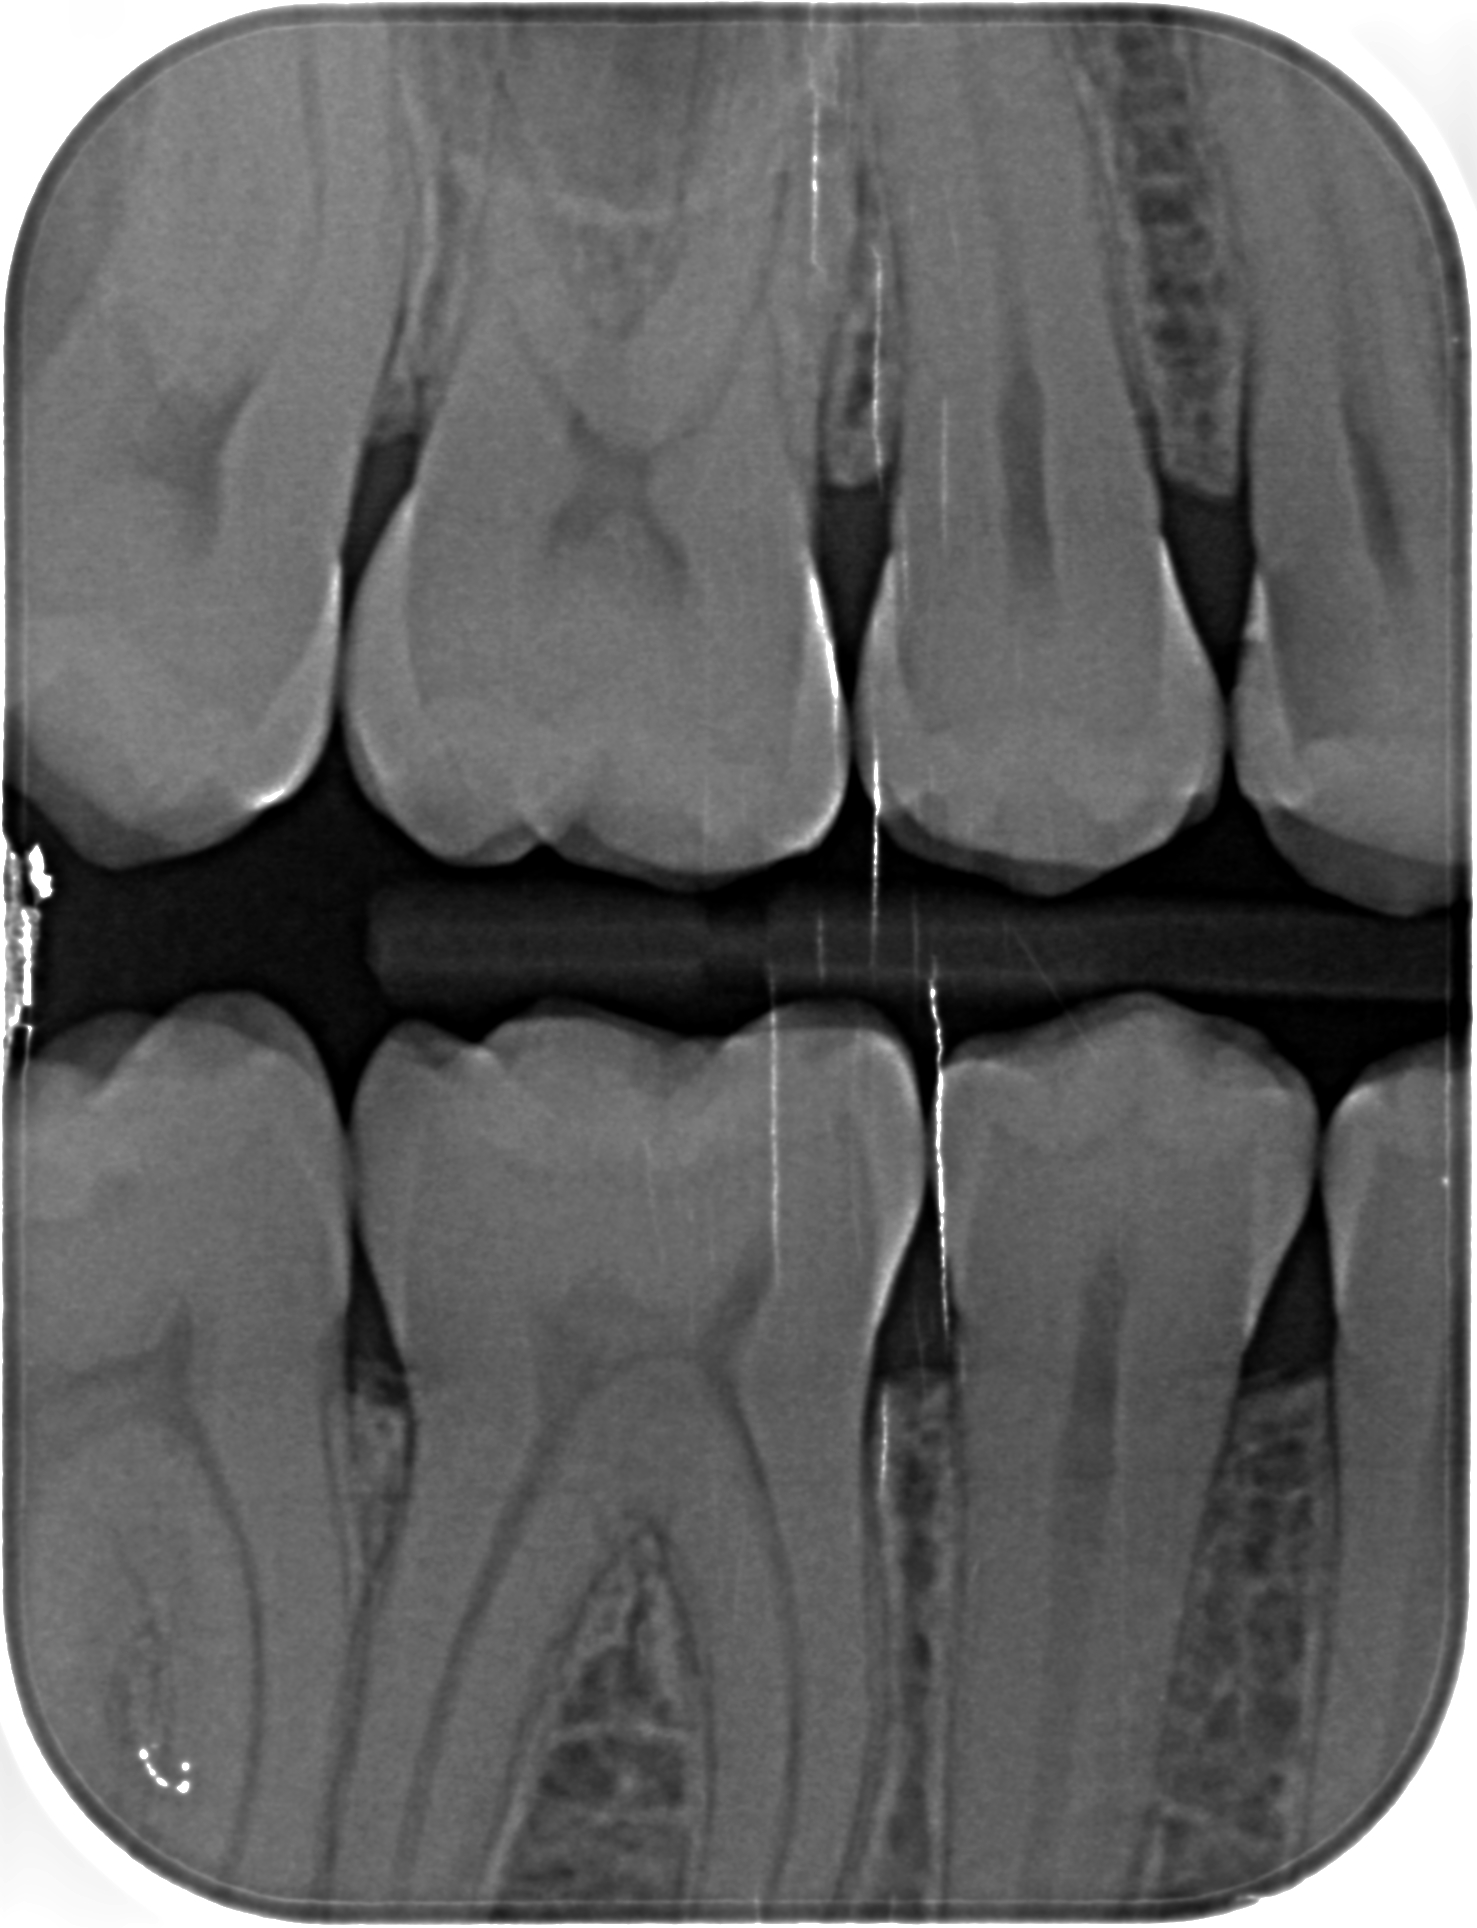

ho fatto una visita dal dentista dove ad occhio nudo ha visto qualche carie e ha poi pensato di fare le lastrine che ho riportato sotto, dove ci vede 7 carie.

Ho fatto poi una seconda visita da un altro dentista dove ad occhio nudo non ha visto niente (strano perchè le igeniste dentali vedevano una carie) ma nelle lastrine ha visto 5 carie

mi potete dire quante carie ci vedete voi e se sono negli stessi denti indicati negli schemi allegati?